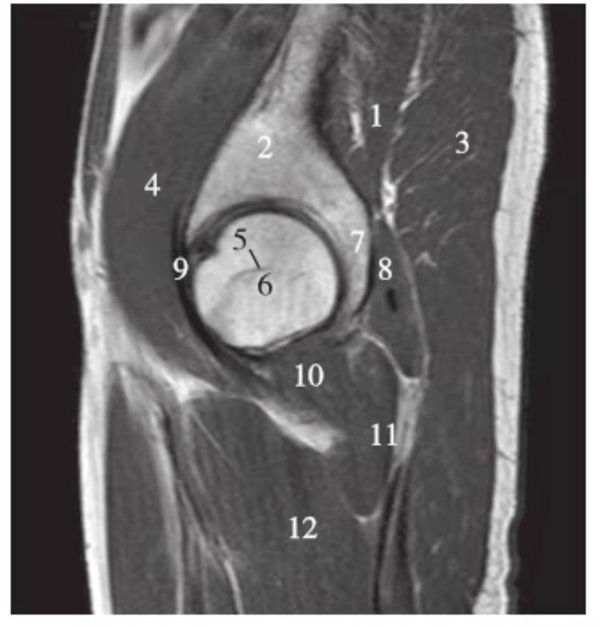

矢状位

正常髋关节经股骨头内缘层面T1WI像

1.髂骨;2.臀大肌;3.圆韧带;4.股骨头;5.坐骨;6.闭孔外肌;7.耻骨肌;8.大收肌

正常髋关节经股骨头中心层面T1WI像

1.臀中肌;2.髂骨;3.臀大肌;4.髂腰肌;5.股骨头骺线;6.股骨头;7.髋臼后唇;8.梨状肌;9.关节囊及髂股韧带;10.闭孔内肌;11.股方肌;12.大收肌